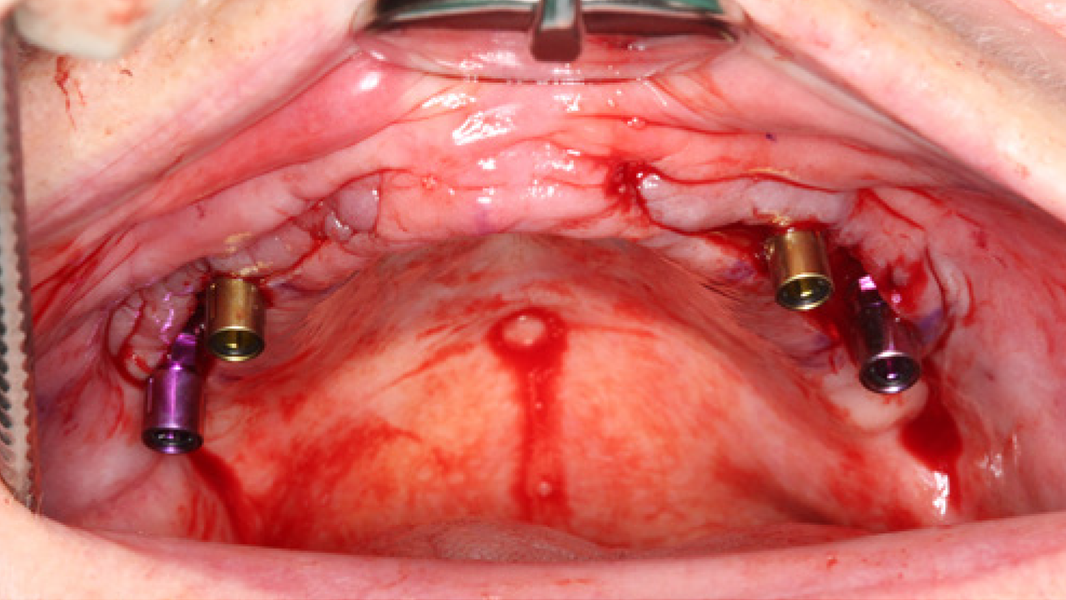

- Die schnelle Remodellierung von MinerOss A verkürzt die Wiedereingliederungszeit und ermöglicht die Implantation nach 3–4 Monaten.9, 10

- MinerOss A remodelliert vollständig in den Knochen des Patienten, ohne dass, wie die histologische Kontrolle zeigt, avitale Reste zurückbleiben.3

- MinerOss A stellt eine verlässliche Alternative zu autologem Knochen dar, die eine hervorragende Regenerationsfähigkeit4 und eine geringere Patientenbelastung aufweist.11